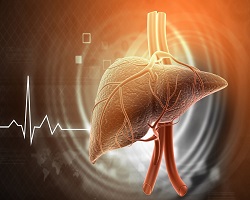

АЛКОХОЛНА ЦИРОЗА ЈЕТРЕ

Алкохолна болест јетре представља један од водећих узрока хроничних обољења јетре широм света. Алкохолна цироза јетре је завршни стадијум овог обољења и настаје као последица дуготрајног и прекомерног уноса алкохола. Карактерише се неповратним оштећењем јетреног паренхима, развојем фиброзе и нарушавањем нормалне структуре јетре, што доводи до смањења њене функције и бројних компликација.